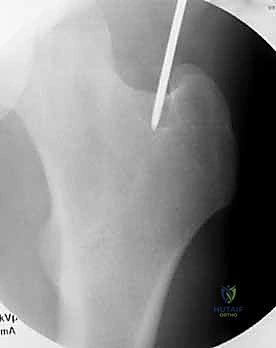

يتم عمل شق جراحي صغير (حوالي 3-5 سم) في منطقة الورك أعلى المدور الكبير (Greater Trochanter) أو الحفرة الكمثرية (Piriformis Fossa). يتم إدخال سلك توجيهي (Guide Wire) بدقة متناهية تحت جهاز الأشعة.

يتم إدخال المسمار المعدني بعناية فائقة فوق السلك التوجيهي حتى يعبر منطقة الكسر ويستقر في الجزء السفلي من الفخذ.